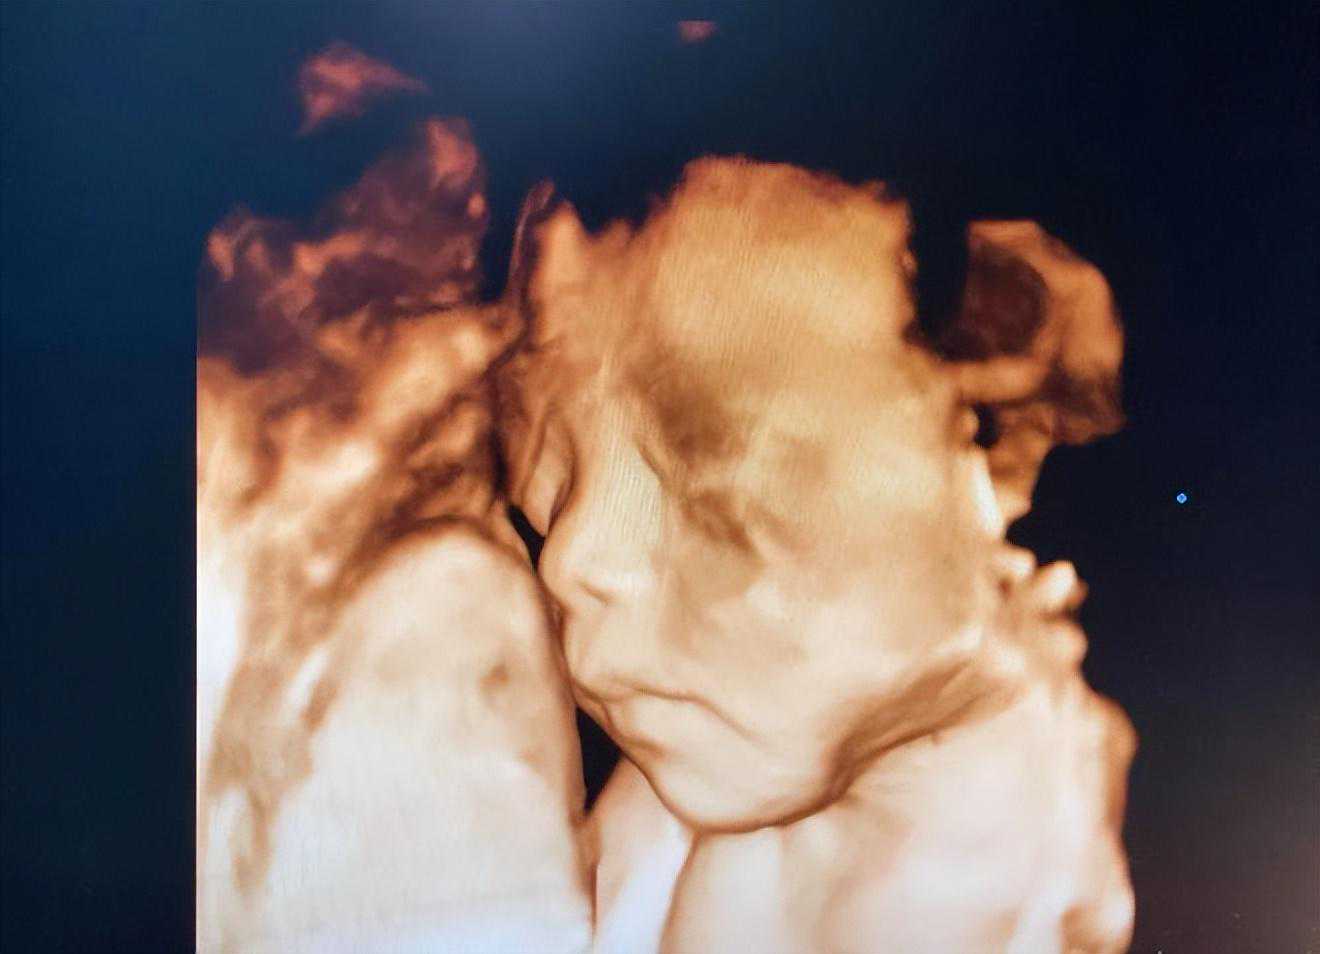

孕22-26周三维超声检查孕22-26周的时候,是看到宝宝最好的时机,医生会做一次完整的结构筛查。

这次检查主要为检查胎儿是否患有重大畸形,对颅内结构、心脏结构、胃泡、双肾、膀胱、肠管、四肢长骨做细致检查,从头到脚采集宝宝很多的图像,仔细观察是否有问题。

要做好这次检查,需要天时地利人和,医生有技巧,宝宝要配合、能动动,不要趴着睡,最好将脸朝向医生。

有时候医生觉在孕妈妈肚子里不动,会让孕妈妈出去转一圈散个步再回来,等着宝宝整个身子转过来再看,因此这次检查时间会比较久,是为了检查得更加准确和完整。